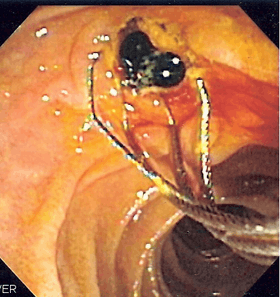

![]() Duodenoscopic image of two pigment stones extracted from common bile duct after sphincterotomy. | |

When needed, the opening to the ampulla can be enlarged by a cut (sphincterotomy) with an electrified wire called sphincterotome and access into the bile duct obtained so that gallstones may be removed or other therapy performed.

Other procedures associated with ERCP include the trawling of the common bile duct with a basket or balloon to remove gallstones and the insertion of a plastic stent to assist the drainage of bile. Also, the pancreatic duct can be cannulated and stents be inserted. The pancreatic duct requires visualisation in cases of pancreatitis.